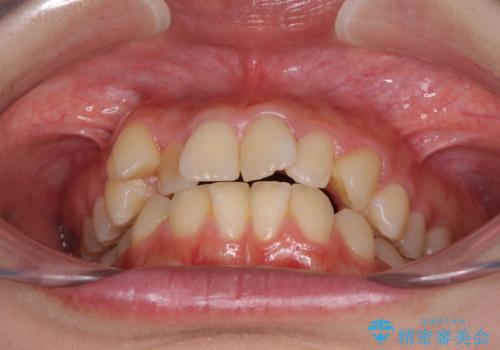

- 前歯のデコボコを気にして来院された患者様です。

本人は気づいていませんでしたが、下顎前歯が2本欠損しており、上下の歯列がアンバランスとなりデコボコになっていました。

上下のバランスを取るため、上顎左右第一小臼歯2本を抜歯し、ワイヤー矯正を行うこととしました。